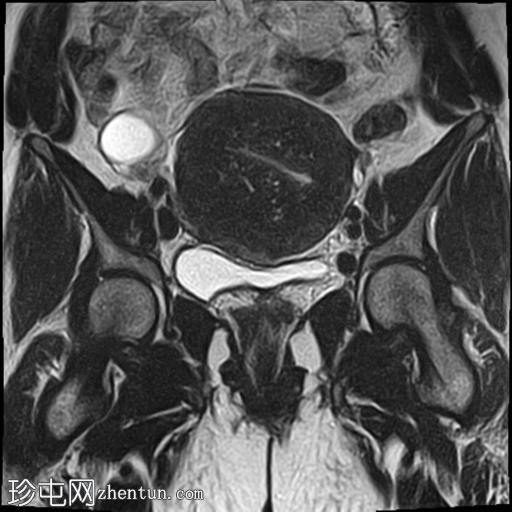

冠状位

T2加权像

子宫增大,子宫内膜-肌层交界区弥漫性增厚,T1加权像呈中等信号,最高达45 mm;T2加权像呈低信号,内含多个小的高T2信号灶,提示月经出血渗入异位子宫内膜组织,符合弥漫性子宫腺肌症的

影像

学表现。

卵巢可见多个小的单房囊肿,无分隔或实性成分,最可能是浆液性包涵囊肿。

MRI表现最符合弥漫性子宫腺肌症。